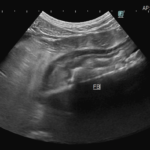

1週間前に団子を串ごと誤飲した可能性があるワンコが急にぐったりしているとのこと。すぐに地元の救急病院を受診すると異物による胃穿孔が疑われました。外科的な摘出と腹膜炎によるクリティカルケアが予想されたため紹介来院しました。開腹後、竹串による胃穿孔が確定されました。腹膜炎も同時に起こっています。穿孔創を封鎖し、腹腔洗浄とドレインの設置を行いました。幸いにも48時間後に食欲が出て退院となりました。愛犬が竹串を誤飲してしまったら、命に関わる事態に発展する可能性もあるため、早めに内視鏡による摘出をお勧めします。このような異物を発見するためにはエックス線よりも超音波検査が非常に有効です。